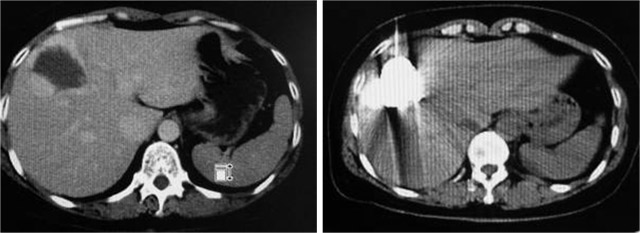

以下是成功病例的CT影像对比:

男,68岁,肝左叶巨大血管瘤,肝动脉栓塞后,肿瘤消失

女,48岁,肝右叶海绵状血管瘤,CT引导经皮穿刺平阳霉素碘油乳剂注射